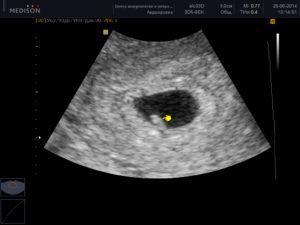

УЗИ – достоверный способ убедиться в том, что произошло прикрепление оплодотворенной яйцеклетки к стенке матки. В зависимости от срока, врач увидит только плодное яйцо или развивающегося в нем эмбриона.

На УЗИ зарождение новой жизни можно увидеть только при прикреплении зиготы к стенке матки, что происходит только на 7-10 день после зачатия. Часто врач на маленьком сроке видит в матке плодное яйцо, но не наблюдает в нем эмбриона.

Примерно с 4 акушерской недели врач может отметить наличие плодного яйца, изменившуюся структуру миометрия и другие косвенные признаки, указывающие на наступившую беременность.

Расшифровкой данных ультразвукового исследования должен заниматься только квалифицированный специалист. На первом УЗИ специалист определяет:

- Наличие каплевидного или округлого гипоэхогенного образования, диаметр которого составляет 0,3-0,5 см. От срока зависит и размер.

- Образование должно быть окружено тонкой оболочкой. Данное образование и есть плодное яйцо.

- Наличие желтого тела.

Во время первого ультразвука специалист-диагност выявляет образование с повышенной эхогенностью. Так выглядит плодное яйцо, величина которого позволяет судить о сроке данной беременности.

Ещё на мониторе будут видны желточный мешок, расположение зародыша, толщина внутреннего слоя матки. Врачи убедятся в отсутствии у женщины воспалений, полипов, кист и опухолей. Расшифровывать данные должен только профильный диагност.

Во время первого УЗИ обнаруживаются:

- круглое или каплевидное образование с низкой эхогенностью размером 3-5 мм. Его размер определяет срок;

- тонкая оболочка вокруг развивающегося ребёнка;

- жёлтое тело – оно вырабатывает прогестерон, способствующий сохранению плода.

На ранних сроках беременности можно различить такие признаки:

- можно увидеть круглое или овальное образование;

- диаметр образования будет составлять около 4-5 миллиметров;

- вокруг него можно увидеть тонкую оболочку;

- во время маточной беременности плод будет находиться в углу матки;